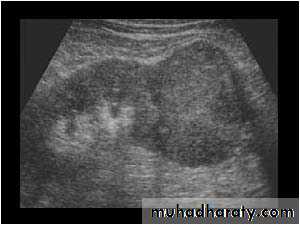

Simple cysts

Very common.

Filled with clear fluid(i.e anechoic).

Show obvious echoes from the front and back walls and posterior acoustic enhancement.

Most are spherical in shape.

Imperceptible walls

Solitary or multiple ,unilocular (simple)or have septations (not a simple cyst)

If contain low level echoes in dependent portion complicated by Hhg or infection.

No further investigations are needed.

ADPKD:

• Familial disorder

• Age (35-55 years)

• Presented with HTN, renal failure and hematuria.

• Bilateral disease.

• Cysts may also be seen in other organs like liver and pancreas .